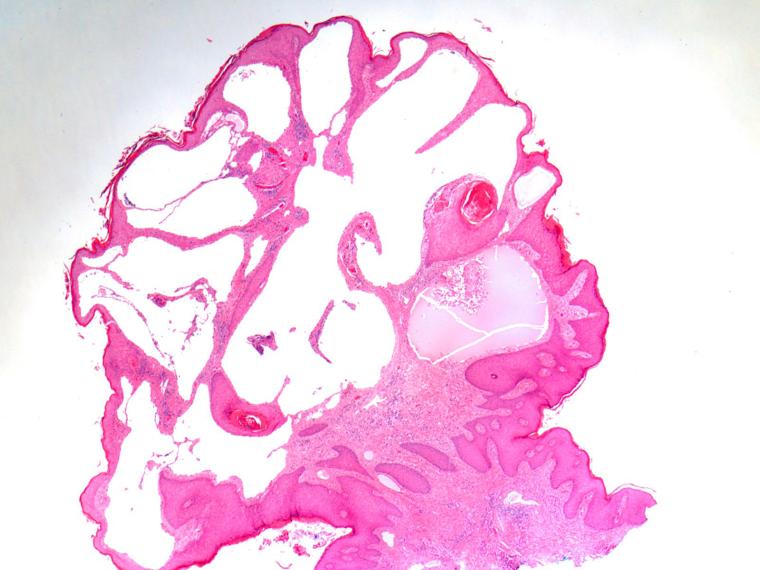

Acquired lymphangioma circumscriptum of the genitals in an individual with chronic hidradenitis suppurativa.

Acquired lymphangioma circumscriptum of the genitals in an individual with chronic hidradenitis suppurativa.患有慢性化脓性汗腺炎个体的获得性局限性生殖器淋巴管瘤。